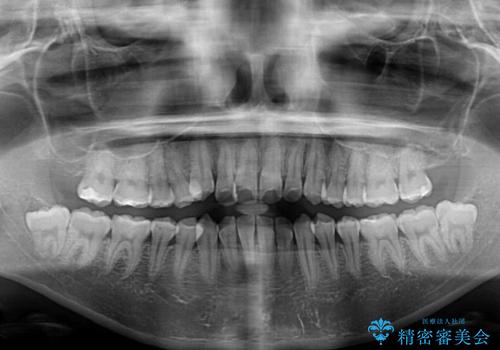

- 前歯の突出感とクロスバイトが気になり、インビザラインによる矯正治療を希望して来院された患者様です。

上顎側切歯(上の真ん中から2番目の歯)が舌側転位している場合、インビザラインでは仕上げきれないことが多く、更には無理して動かそうとすると歯髄壊死を起こすリスクが高いと言われています。

インビザラインで歯列を移動する前に、上顎前歯をワイヤー矯正で整え、その後上下歯列をインビザラインにて矯正治療を行うこととしました。